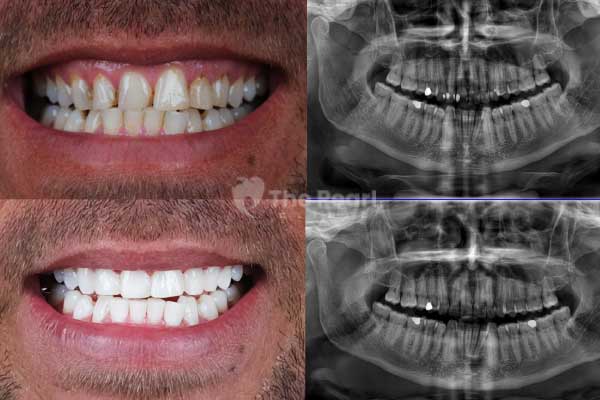

There was a time when smiles were filled with silver and even gold decorations. In the past, highly durable silver amalgam materials were used. However, their negative aesthetic effects have led to the adoption of newer materials. Primarily, we refer to composites. These are a type of resin that matches the color of the bone like the tooth. As mentioned earlier, composites fill the void, and since they harden with light, they are cured with a special light.

Can a Tooth with a Filling Be Whitened?

If possible. The only disadvantage is that the color of the filling does not change with whitening, remaining the same as the enamel. As a result, the filling may be slightly more visible after whitening. However, it can always be replaced with a new one that matches the current tone of the prosthesis. In any case, what should never be done is whitening when there is a cavity without filling, as it can worsen infections.